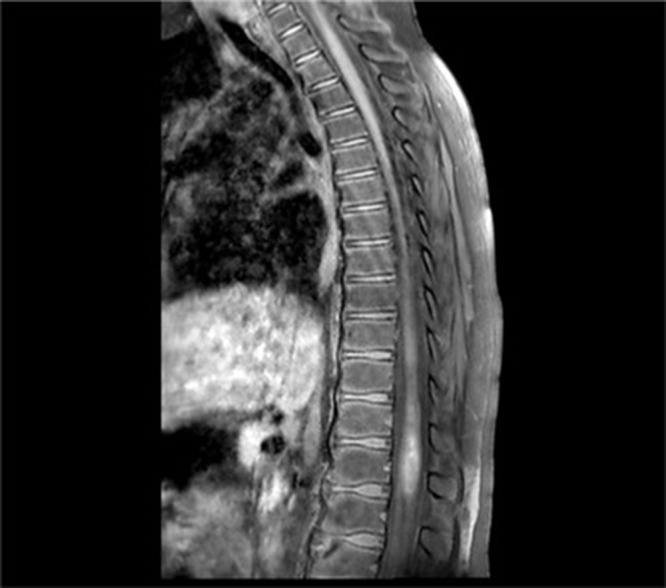

Case presentation: The case of acute transverse myelitis in a 12-year-old child corresponds to the existing definition of a vaccine-associated paralytic poliomyelitis case: a temporal relationship between the onset of flaccid paralysis and the administration of oral polio vaccine and the duration of paralysis. The child developed flaccid paralysis 18 days after (August, 2024) the administration of oral polio vaccine and persisted for more than 60 days from the onset of the disease. Vaccine virus type 3 was isolated from the feces. However, the child received 2 doses of inactivated oral polio vaccine and 1 dose of bivalent (types 1 and 3) oral polio vaccine before the disease. The child did not have an increase in the titer of antibodies in paired sera to polioviruses types 1 and 3. Spinal cord magnetic resonance imaging revealed an intramedullary focus with hyperintense MR signal on 2WI, 2FS at the level of the spinal cord cone (Th11-L2), which spread across the entire diameter and unevenly accumulated paramagnetic. These changes were characteristic of acute transverse myelitis.